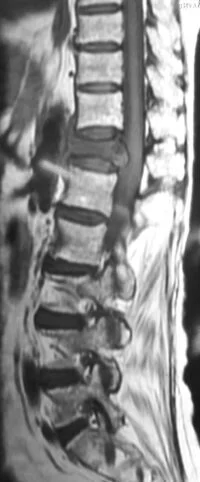

Based on these tests, or sometimes, in the presence of some very significant signs or symptoms, you may be asked to undergo MRI scanning. Plain x-rays demonstrate bony features; while MRI demonstrates the spinal cord, its nerve roots, the intervertebral disc between the two bones of the spine. Both these tests are complimentary in nature; doing one does not necessarily mean that the other one is not needed.